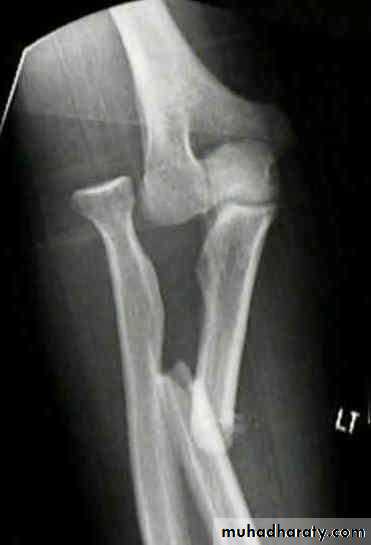

The injury described by Monteggia in the early nineteenthth century (without benefit of x-rays!) was afracture of the shaft of the ulna associated with dislocation of the proximal radio-ulnar joint; the radiocapitellar joint is inevitably dislocated or subluxated as well. More recently the definition has been extended to embrace almost any fracture of the ulna associated with dislocation of the radio-capitellar joint, including trans-olecranon fractures in which the proximal radioulnar joint remains intact.

Usually the cause is a fall on the hand; if at themoment of impact the body is twisting, its momentum may forcibly pronate the forearm. The radial head usually dislocates forwards and the upper third of the ulna fractures and bows forward .

The ulnar deformity is usually obvious but the dislocated head of radius is masked by swelling. A useful clue is pain and tenderness on the lateral side of the elbow. The wrist and hand should be examined for signs of injury to the radial nerve.X-ray

With isolated fractures of the ulna, it is essential to obtain a true anteroposterior and true lateral view of the elbow. In the usual case, the head of the radius (which normally points directly to the capitulum) is dislocated forwards, and there is a fracture of the upper third of the ulna with forward bowing.X-ray